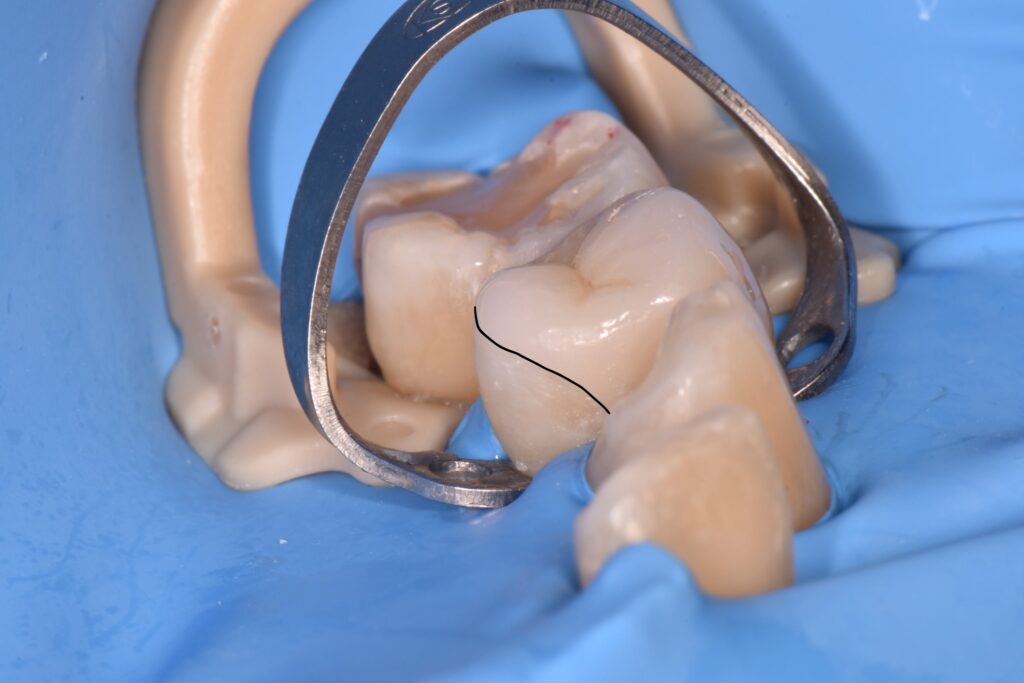

実際のVonlayを装着する際の写真です。

セラミックを接着する際は、唾液や呼気中の水分によって接着力が著しく低下してしまうため、まずはこのようにラバーダム防湿と呼ばれる方法で歯だけを見えるような状態にして、完全に歯の表面を乾燥させます。

今回は手前の歯のため審美的な回復も必要となるため、歯の表面も覆うVonlayとしています。